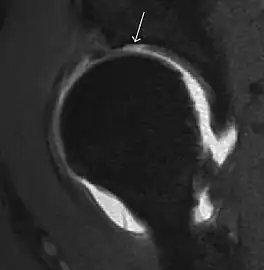

Most of the angles and measurements described in the plain radiograph section can be accurately reproduced on MRI. In addition, the superiority of MRI resolution with intra-articular contrast allows detection of labral and chondral abnormalities that may influence the choice of medical, percutaneous, or surgical management (Figure 9).[1]

Figure 9:

-

Sagittal T1 weighted image showing anterosuperior labral tear.[1] -

Sagittal T1 weighted image showing chondral lesion.[1] -

Sagittal CT-arthrography showing posteroinferior chondral injury.[1] -

Coronal CT-arthrography (d) showing ligamentum teres tear.[1]

MR arthrography has proven superior in accuracy when compared to native MR imaging. It is considered the best technique to assess the labrum. Knowledge of the normal variable morphology of the labrum helps to differentiate tears from normal variants. A triangular shape is most commonly seen in 66% of asymptomatic volunteers, but round, flattened, and absent labra can also be found in asymptomatic populations. MR arthrography has demonstrated sensitivity over 90% and specificity close to 100% in detecting labral tears. Loose bodies are demonstrated as filling defects surrounded by the hyperintense gadolinium.[1]

Association between labral tears and chondral damage has been demonstrated. This underscores the interaction between cartilage and labrum damage in the progression of osteoarthritis. Chondral damage to the posteroinferior part of the acetabulum as a contrecoup lesion occurs in approximately one-third of pincer cases secondary to persistent abutment on the anterior part of the joint leading to a slight posteroinferior subluxation. This is considered a bad prognosis sign.[1]